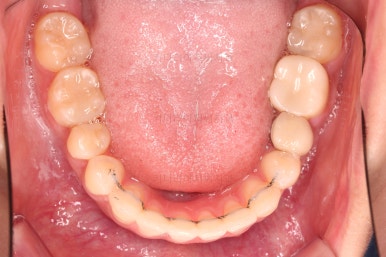

틈이 다 없어졌고, 교합도 양호합니다.

무엇보다 임플란트 없이 결손부위가 깔끔하게 채워졌고요.

매우 다행으로 사랑니도 다 있었기 때문에 마치 큰 어금니가 다 있는 것과 같은 상황이 되었습니다.

총 치료기간도 2년 반, 30개월이 걸렸습니다.

3년 이상 봐야 되는 부산사랑니교정 치료라고 말씀 드리고 시작했음에도 예상보다 훨씬 빨리 종료 되어 매우 만족스러운 치료였습니다.

입안의 모습은 더할나위 없이 잘 개선되었고요.

상하좌우 이 뽑은 위치와 크기가 달라 이정도 중앙선은 매우 잘 맞는 상황인거고요.